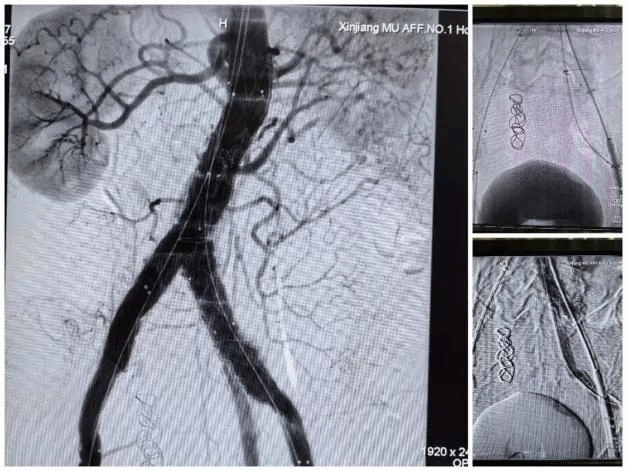

手术当天,在麻醉科团队和手术室专业护理组的细心配合下,手术团队顺利完成了“腹主动脉覆膜支架腔内隔绝术+腹主动脉开窗分支覆膜支架置入术(左肾副肾动脉及左侧髂内动脉)+腹主动脉分支覆膜支架置入术+经导管内髂内动脉栓塞术+腹主动脉造影+腹主动脉球囊血管成形术”,术后经造影检查,提示手术成形效果好,各分支动脉血流通畅,腹主动脉瘤成功隔绝,右髂内动脉成功栓塞,避免了内漏发生。术后在呼吸重症医学中心团队的精心监护下,患者很快转回普通病房,并顺利康复出院。整个诊疗过程中多学科医护人员精密合作,克服了重重困难,为患者的安全和健康全力以赴。